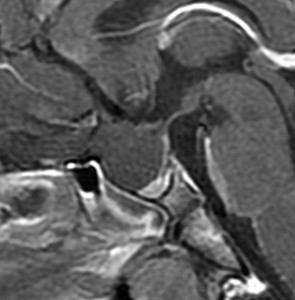

この患者さんは軽い下垂体機能低下症で発症しました。蝶形骨洞の中にのう胞が拡大していて,下垂体がぺったんこです。鞍上部には全く伸びていないので,視神経交叉は正常に見えます。この手術はとても簡単です,嚢胞をぷつんと破って液体を排出するだけにした方がいいでしょう。何故なら下垂体がうすく菲薄化funningしているので嚢胞壁を摘出しようとすると前葉機能を低下させるリスクが高いからです。